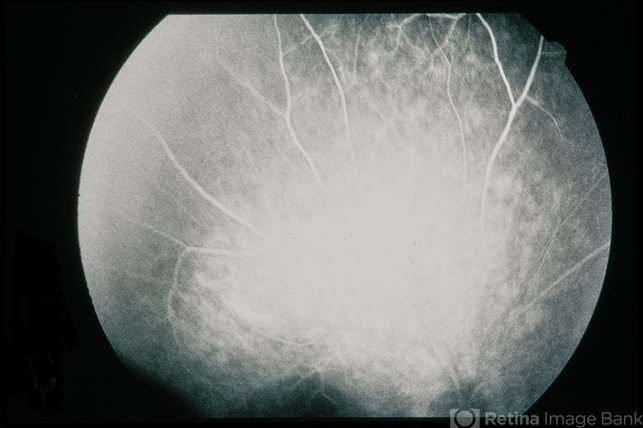

- Plaquenil Toxicity

- 60-year-old female with plaquenil toxicity.